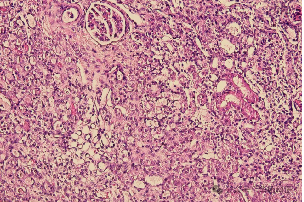

The UUO model, as a model of renal fibrosis, is characterized by interstitial inflammation, excessive production of extracellular matrix, atrophy of renal tubular epithelial cells, and tubulointerstitial transformation.

Sham (40x) UUO (40x)